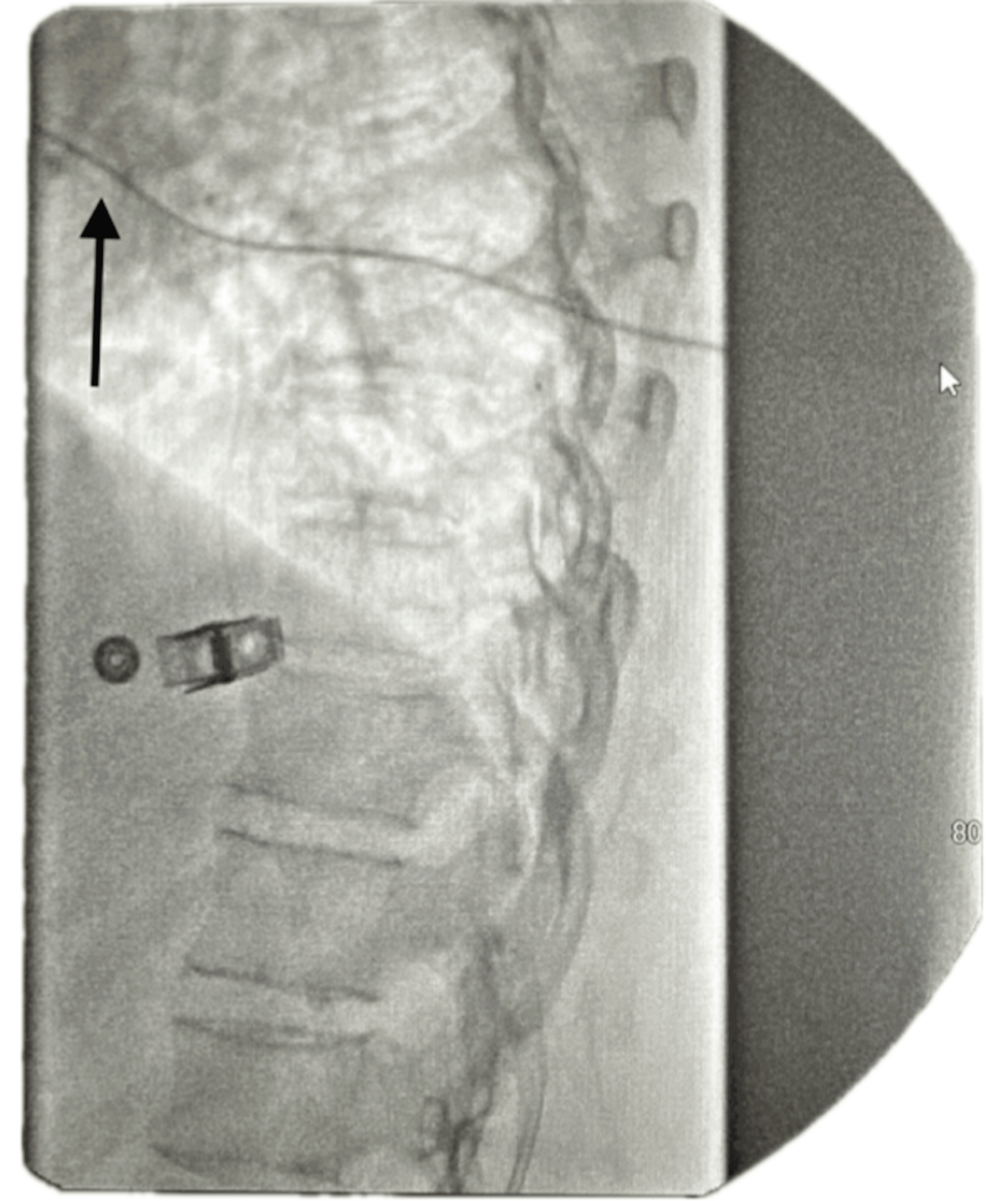

The ITP is programmed to deliver a micro-dose regimen consisting of morphine 2 mg and bupivacaine 2 mg (0.5%) in a total volume of 20 mL. The infusion rate is set at 0.7496 mg/day. The catheter tip is positioned at the T8 level within the intrathecal space, as confirmed by imaging (Figure 1). The low reservoir alarm is set to trigger at 2.0 mL to ensure timely refilling and management.

An IV was placed, and the patient was positioned in the left lateral decubitus position with proper padding and spinal alignment. After sterile preparation, the L3-L4 interlaminar space was identified under fluoroscopy. The skin was anesthetized with 2% preservative-free lidocaine, and a small incision was made. A 14-gauge Touhy needle was advanced into the intrathecal space, with positive CSF flow confirmed on fluoroscopy. An intrathecal catheter was inserted and advanced to the T9 vertebral level.